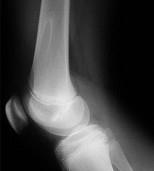

男,13岁,运动后膝痛,请结合影像图像,选择最可能的诊断()A.正常影像B.动脉瘤样骨囊肿C.骨软骨瘤D.成骨细胞瘤E.骨样骨瘤

问题 男,13岁,运动后膝痛,请结合影像图像,选择最可能的诊断()

选项 A.正常影像 B.动脉瘤样骨囊肿 C.骨软骨瘤 D.成骨细胞瘤 E.骨样骨瘤

答案 C